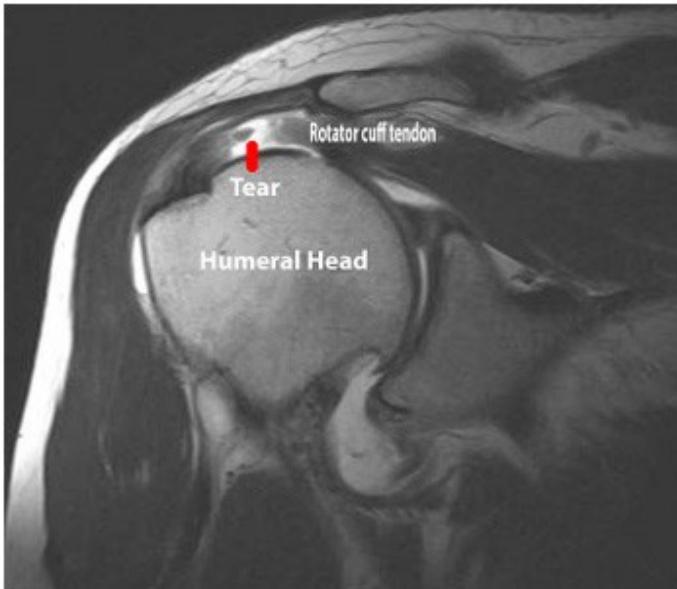

Imaging

Question: What do you see on these images?

Case Study 5: Rotator Cuff Tear

A 55-year-old lady presented in clinic complaining of right shoulder pain.

History

- No history of trauma (insidious onset)

- Pain pattern: Night pain is a prominent feature

- Functional decline: Cannot raise hand above head, symptoms worsening over time

- Bilateral involvement: Other shoulder is less severe

- Treatment history: Physiotherapy failed to improve symptoms

Examination

- Symmetrical shoulders on inspection

- Muscle atrophy: Notable atrophy of shoulder muscles

- Tenderness: Localized tenderness at greater tuberosity (GT)

- Range of motion: Limited abduction

- Strength testing: Weak abduction & external rotation

- Special tests:

- Neer’s test: Positive ✅

- Hawkin’s test: Positive ✅